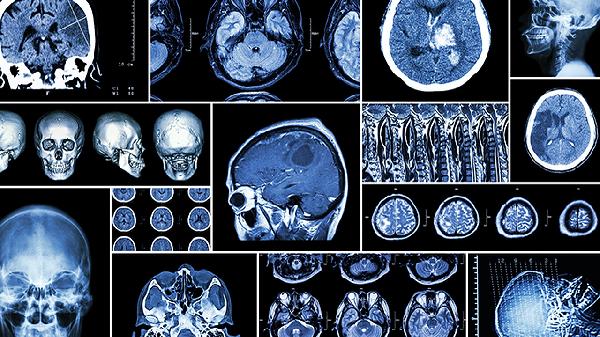

如症状严重影响生活,可遵医嘱使用盐酸帕罗西汀片治疗焦虑引起的思维奔逸,劳拉西泮片缓解急性发作,阿戈美拉汀片调节睡眠节律。这些药物通过调节γ-氨基丁酸或5-羟色胺系统发挥作用,需严格遵循医嘱调整剂量。